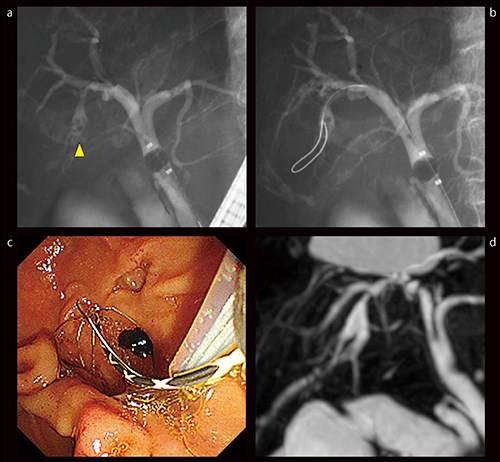

症例4は、77歳、男性、胆道再建後の治療に難渋した肝内結石の症例である。胆囊がん術後4年で、胆管炎を繰り返していた。MRCPでは左右肝管合流部に肝内結石を認めた。小腸鏡では吻合部の狭窄を認め、8mm径のバルーンカテーテルで高圧に拡張したが、吻合部狭窄のノッチが残存した。結石を可及的に除去したが、処置後のMRCPでは結石の残存が確認された。2回目の治療では、吻合部をバルーンカテーテルで再拡張して結石の除去を試みるも、やはり吻合部拡張が不十分となり結石除去困難であった(図9 a,b)。そこで、胆管金属ステントによる吻合部拡張の戦略に切り替えた(図9 c)。1週間後にステントを抜去しようとしたところ、ステント内に結石が入り込んでいたため、ステントごと結石を除去することができた(図9 d)。

図9 症例4:胆道再建後の治療に難渋した肝内結石症例(77歳、男性)

a:Bra(右前区域枝)内に複数の肝内結石(▶)

b:吻合部が十分に拡張できず、Bra内の肝内結石が残存(→)

c:Braに金属ステントを留置

d:1週間後のステント抜去時、肝内結石はステント内に入り込み、ステントとともに除去に成功した。